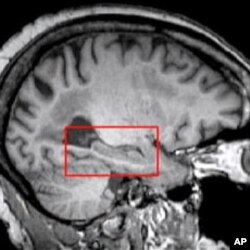

The hippocampus - the red block in another section of the brain - controls memory, and may also be affected by a stroke.

“When we see memory changes in aging, we usually attribute those changes to some sort of functional change or structural change in the hippocampus. What we found was that in silent strokes, the presence of strokes in the brain was also related to memory functioning,” Brickman said.